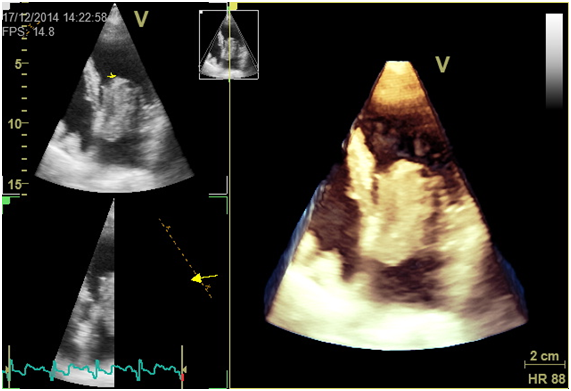

We report a case of a 57-year-old female, with previous history of smoking, hyperlipidaemia and history of ischemic stroke without residual deficits. She was ordered a transthoracic echocardiogram (ETT) to rule out cardiac embolism which revealed an echogenic left atrial mass of huge dimensions (5.8x2.8cm) connected by a small pedicle to the interatrial septum and prolapsing into the left ventricle in diastole causing transmitral flow obstruction (Figure 1) (Figure 2). Doppler revealed a mean pressure gradient between left atrium and ventricle of 9.71mmHg (Figure 3). Transthoracic 3D echocardiography allowed a better characterization of the mass and its attachment to the interatrial septum (Figure 4).

Figure 1 Ecocardiographic 4-chamber view showing giant left atrial myxoma prolapsing into left ventricular in diastole.

Figure 4 3D echocardiographic image showing giant left atrial myxoma.